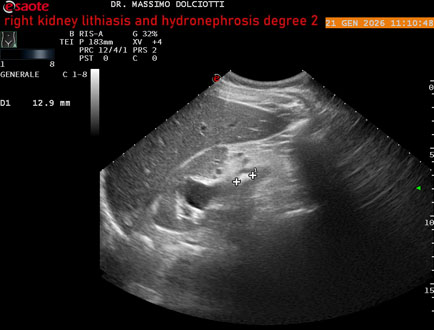

Data inserimento: 22/01/2026

Ecografia del: 21/01/2025

Strumento: Esaote MyLab Eight

Sonda: Convex Multifrequenza 1-8 MHz

Età Paziente: M 27 anni

Motivazione dell'esame: dolore al fianco destro da 3 mesi.

Commento all'esame: le immagini ed il video documentano il rene destro in sede, con ecostruttura disomogenea per evidenza, alla pelvi renale, di immagine iperecogena delle dimensioni di 16,2 mm, con cono d'ombra posteriore, da ricondurre a litiasi ed una formazione simile, di minore entità, al polo inferiore, delle dimensioni di 6,8 mm. Rene dx con diametro longitudinale di 122 mm (v.n. 90-120 mm) x 63 mm e parenchima renale dello spessore di 15 mm (v.n. > 13 mm). Rene dx con idronefrosi di 2° grado.

Conclusioni: litiasi e idronefrosi di 2° grado al rene destro (lithiasis and second-degree hydronephrosis of the right kidney).

In collaborazione: Dr.ssa Marica Manfredi - Ancona, Dr. Ilir Qose - Ancona

Presentazione: Dr. Massimo Dolciotti - Ancona

Elaborazione digitale: Andrea Dini - Ancona